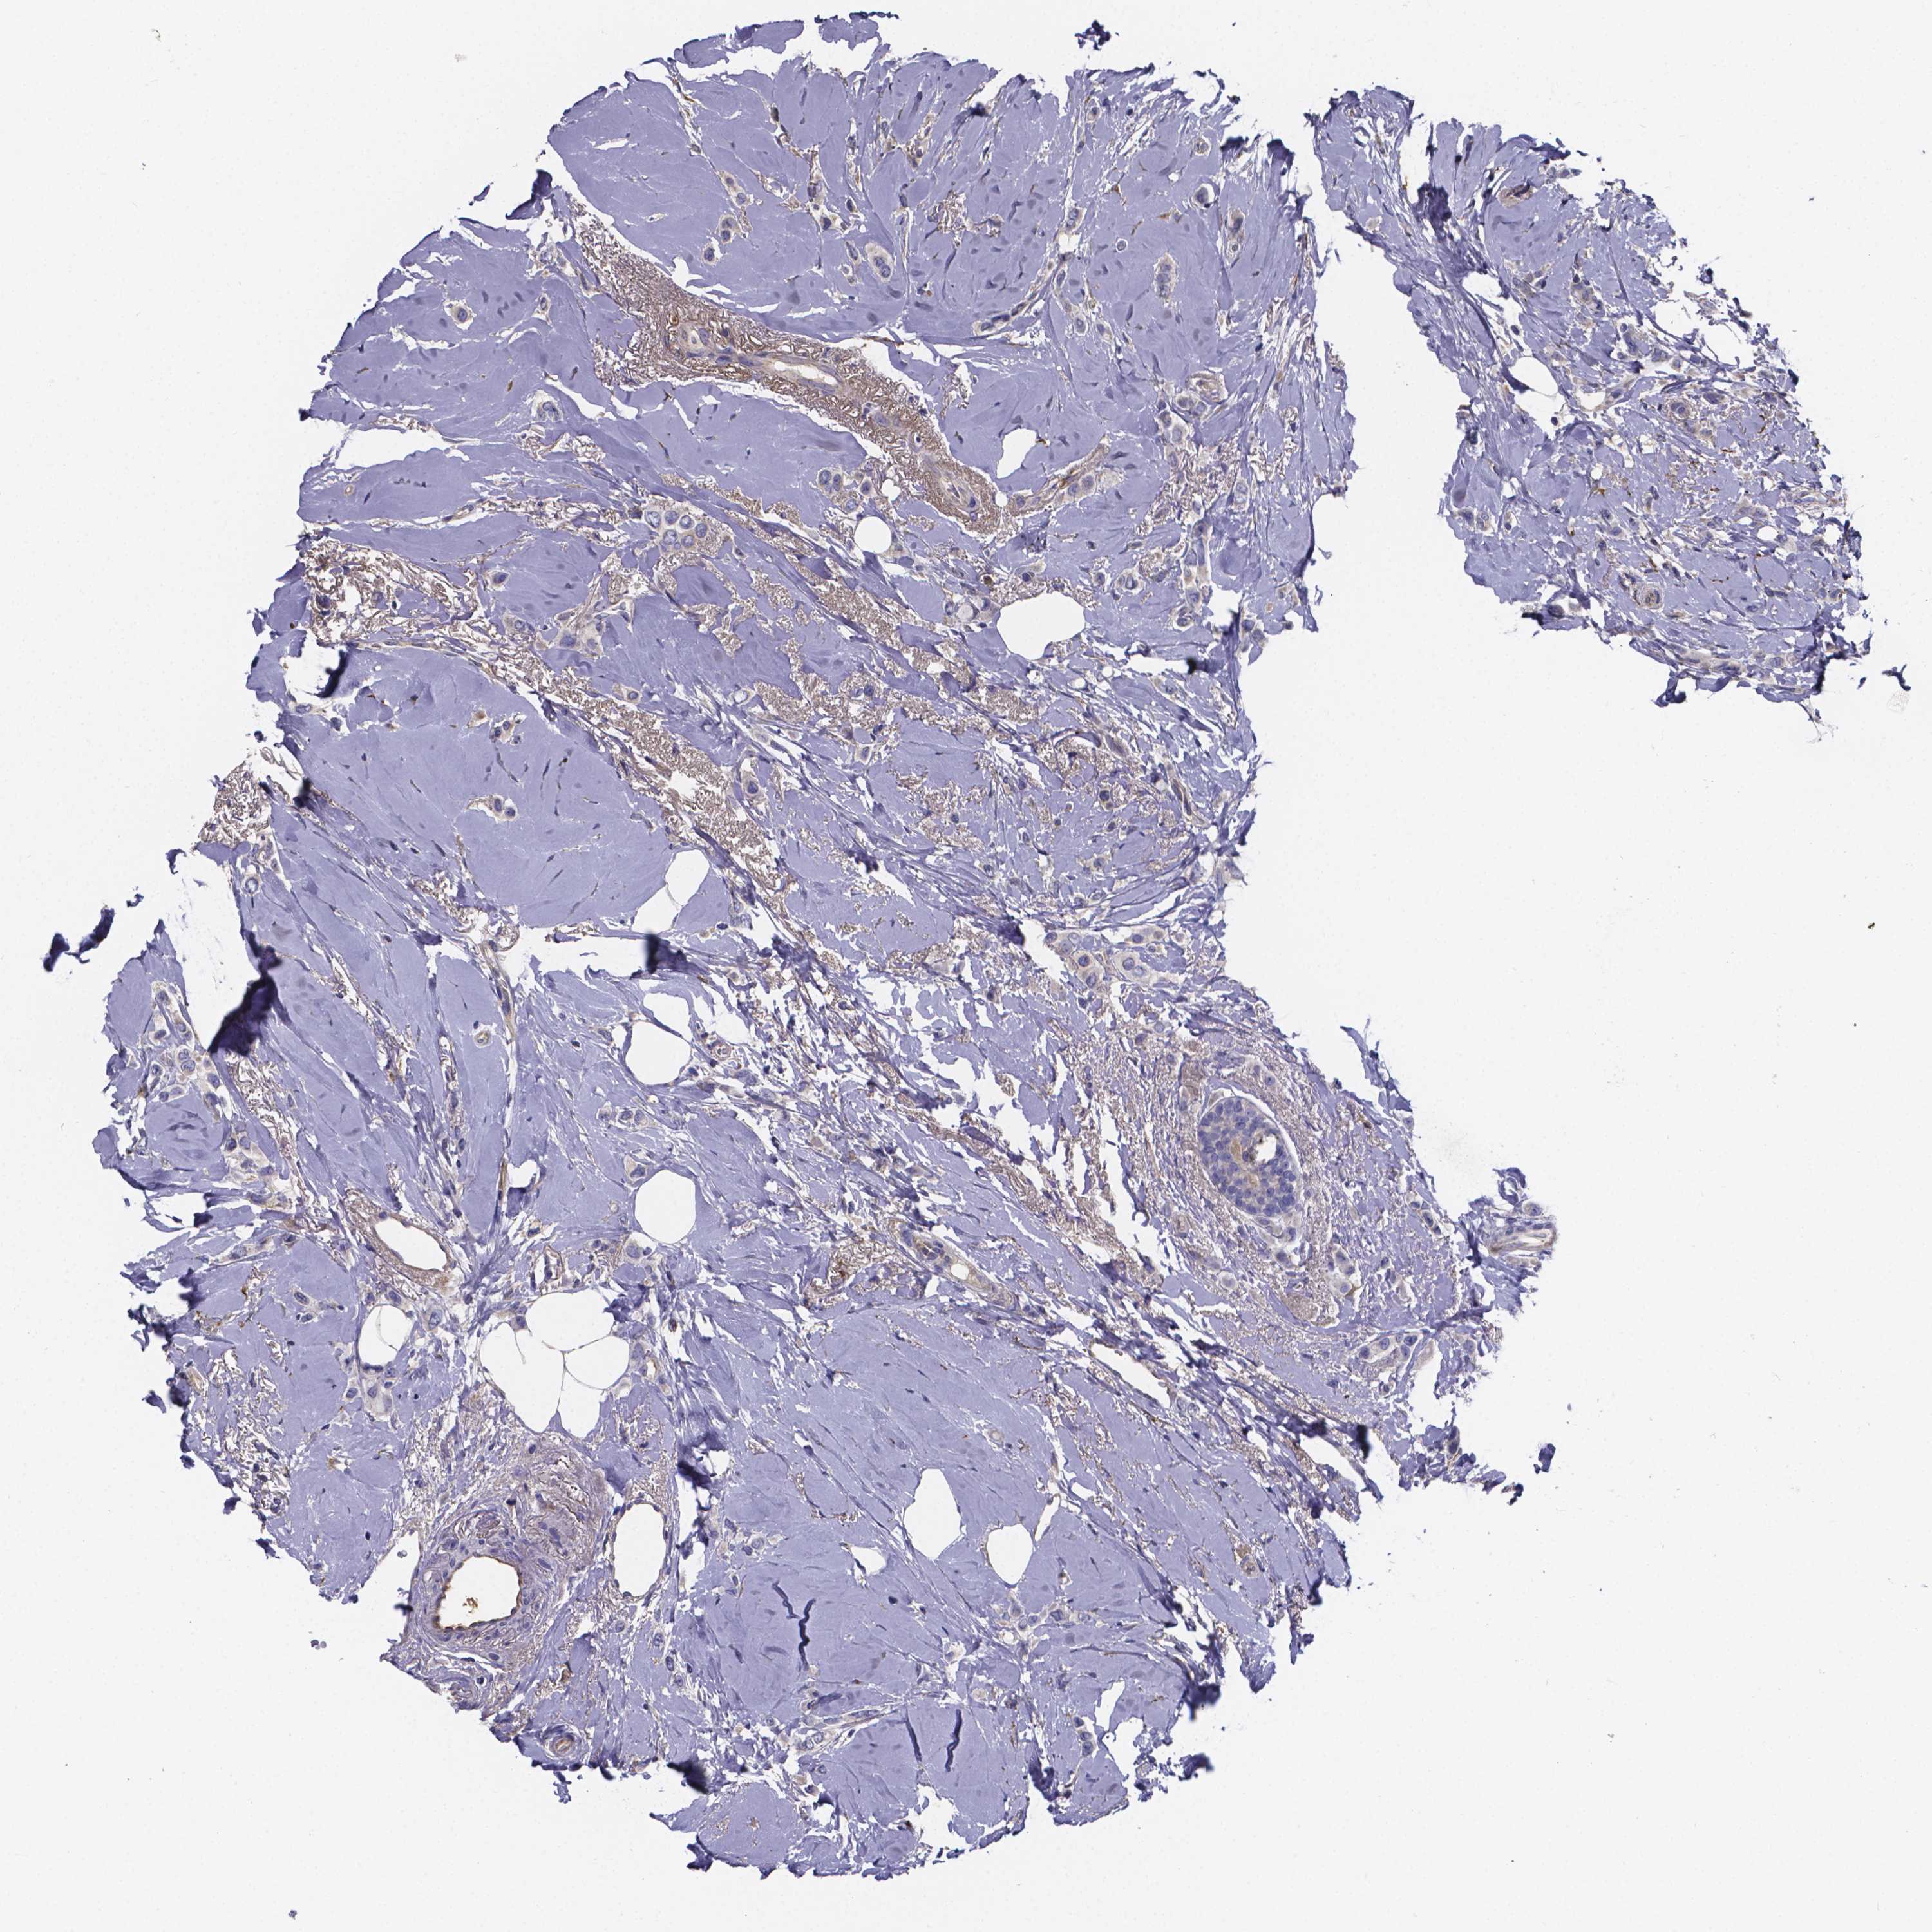

BRCA TCGA BRCA VALIDATION PROTEIN EXPRESSION

ANTIBODIES

AND

VALIDATION